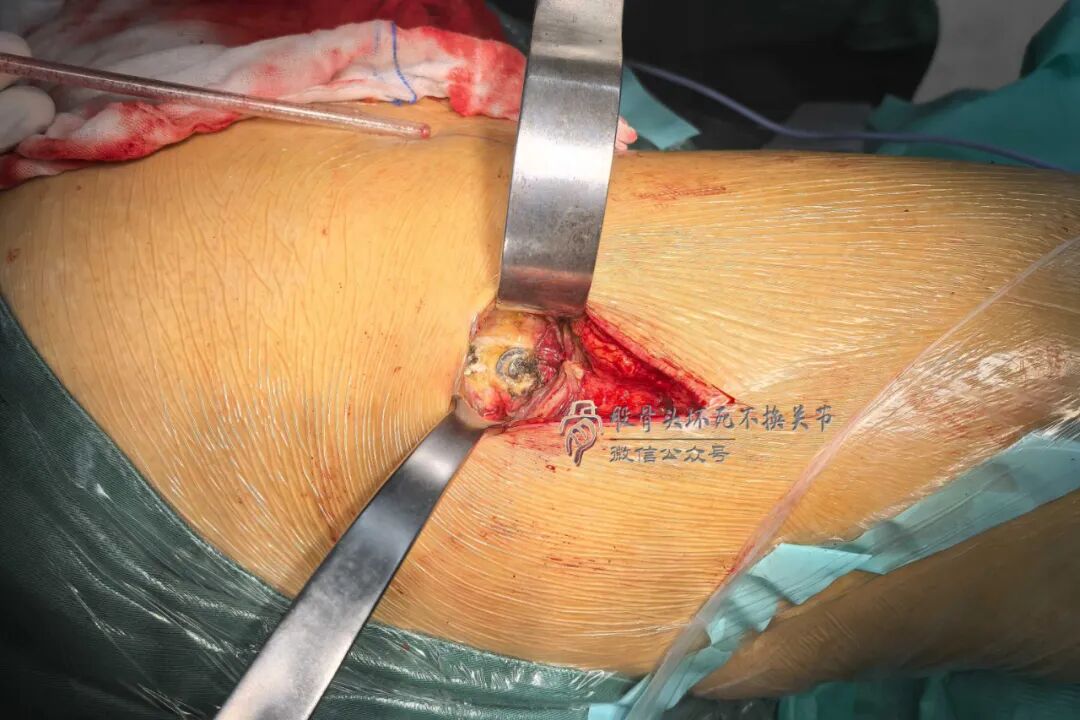

由于岁月已久,关节囊浅层的脂肪层已经萎缩消失,股直肌和髂关节囊肌明显萎缩、粘连,手指也无法摸到关节间隙。

硬邦邦的关节囊瘢痕组织切开,映入眼帘的是疙疙瘩瘩的骨赘——股骨颈前方全是“丘陵”,看不到股骨颈的形状,关节囊完全变成了贴骨疤。

不透视确定股骨颈的准确形状是很难的,摆锯从哪开始动工是没谱的。

但其实有个窍门——依据大转子尖的位置,内斜45°截骨即可。